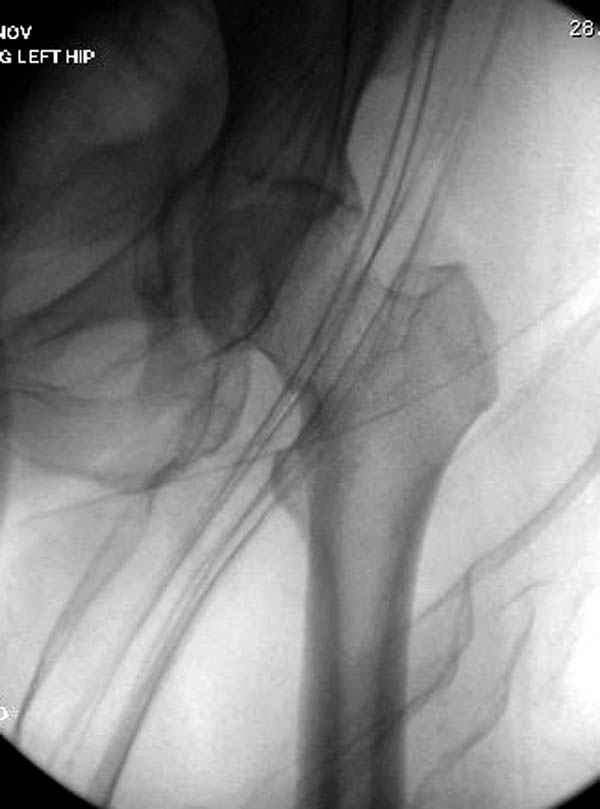

Уважаемые коллеги! С прошедшеми Вас праздниками. Теперь ближе к трудовым будням. Поступила 16 летняя девушка неделю назад. Механизм травмы падение с 5 этажа. Краткий диагноз:закрытый перелом левой ключицы, левого плеча, закрытый вертикально и ротационно нестабильный перелом костей таза:закрытый перелом левой подвздошной кости, переломы лонной кости справа, перелом обоих колонн вертлужной впадины слева;субкапитальный перелом шейки левой бедренной кости со смещением. По тактике лечения таза возникли следующие вопросы: 1. С чего начать - фиксации переломов вертлужной впадины или устранения деформаций таза? 2. Надо ли фиксировать шейку или фиксировать бедро в аппарате вместе с тазом, а после сращения таза планировать ТЭП ТБС? Если имеются еще какие подводные камни, будем рады выслушать.Спасибо.

Долгое ожидание повышает риск АВН головки,

рекомендуется ургентная фиксация шейки в первые сутки, а в дальнейшем таз.

В данный момент скелетное вытяжение поучается через перелом шейки, а фиксированный перелом шейки будет участвовать в процессе вытяжения через каннюлированные шурупы.

Перелом шейки смогли зафиксировать через пару дней, ацетабулум до сих пор не оперирован, на вытяжении.